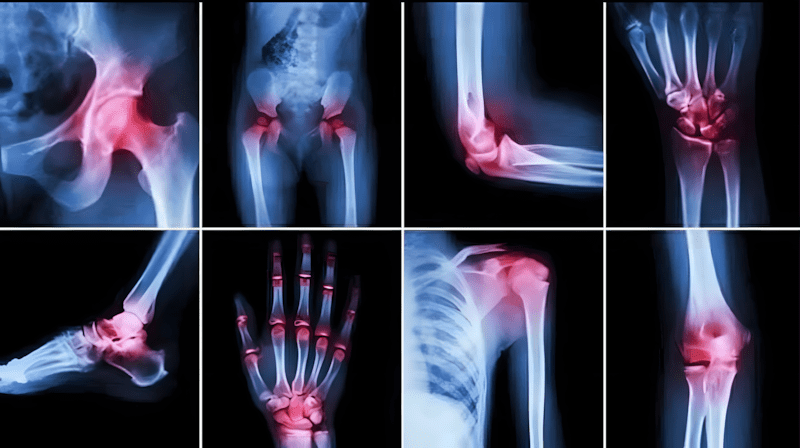

Gewrichtspijn is een van de meest voorkomende gezondheidsproblemen die mensen van alle leeftijden treffen, vooral bij het ouder worden, lange werkdagen of langdurig stilzitten. Gewrichten zijn de punten waar botten samenkomen en het lichaam flexibiliteit en beweging geven. Elke disfunctie of slijtage in deze gewrichten leidt tot aanhoudende pijn en stijfheid, en soms tot problemen met lopen of het uitvoeren van dagelijkse taken.